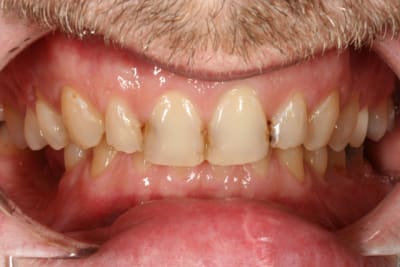

cette patiente que je suis en controle depuis 2 ans, se décide à faire quelque chose pour son sourire.

elle a plein de vieux compos d'une mauvaise couleur, au joints colorés, des dents de couleur pas vraiment toutes pareilles ; et un sourire très gingival.

pour l'occlusion, voilà les photos, il y a effectivement une classe II, plus marquée à droite qu'à gauche

elle a certes un sourire très gingival lié à la classe II, mais est-ce si grave que ça ?

Si on regarde la photo 3, sourire de face, tu doit faire 10 céram en haut, de

5 à 5 (et là, je ne retiens pour pas dire 12...)

Ensuite, tu fais rien pour la couleur en bas ? OK

pour l'attrition ? OK, au pire une goutière nocturne.

Si tu touches 6 dents (3 à 3), ben le sourire ne sera tjs pas trop beau...juste mon pt de vue.